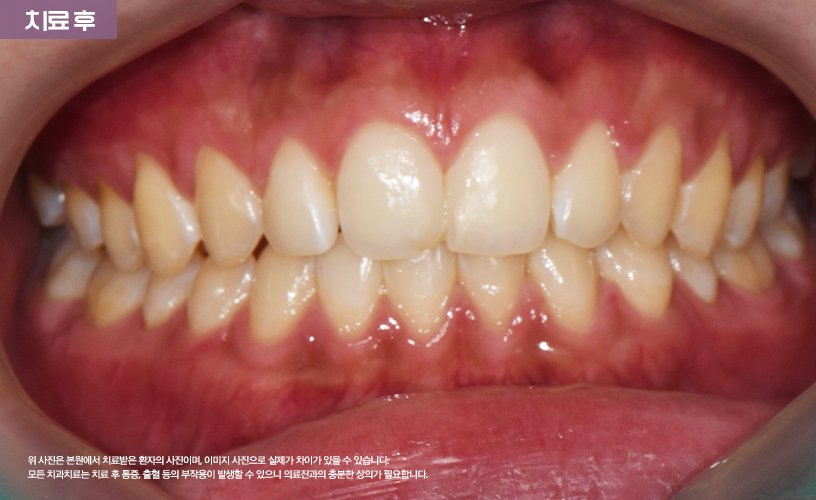

"투명교정 치료 사례"

상기 환자분은 상, 하악 앞니 벌어짐으로 인해

교정 치료를 고민하시다가 본 원에 내원하셨습니다.

본 원에서는 정밀한 검진을 통해 환자분의

앞니 벌어짐 상태를 점검한 다음

기존 일반적인 교정 치료 방식이 아닌

시스루 얼라이너 투명교정 치료가 수립되었습니다.

투명장치를 착용하여 치료가 진행되어

환자분의 일상생활에도 큰 지장을 주지 않으면서도

교정치료가 진행되기 때문에 환자분 역시

매우 만족해하셨습니다.